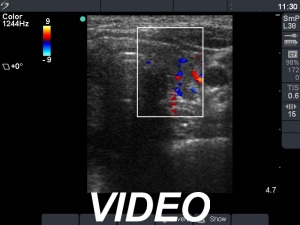

Ultrasonography: The thyroid was moderately hypoechogenic and showed increased vascularity. There was an echonormal nodule in the right lobe with combined perinodular and intranodular vascular pattern.